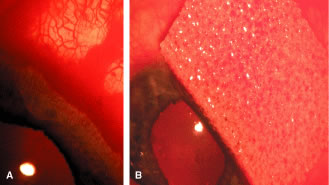

the 10 and 2 o'clock positions of the eye, assumes great significance.  Fig. 9. Indentation gonioscopy. A. The angle appears closed. However, the observer cannot determine whether

this appearance is due to mere contacts between the iris and cornea

or to actual adhesion. B. The goniolens has been pressed against the central cornea, displacing

aqueous into the periphery and showing that the angle is open. C. Indentation gonioscopy displaces the iris posteriorly, showing peripheral

anterior synechiae. (Schwartz LW. Diagnostic evaluation of the patient. In Spaeth GL (ed). Early

Primary Open-Angle Glaucoma: Diagnosis and Management. Boston: Little, Brown & Co, 1979.) Fig. 9. Indentation gonioscopy. A. The angle appears closed. However, the observer cannot determine whether

this appearance is due to mere contacts between the iris and cornea

or to actual adhesion. B. The goniolens has been pressed against the central cornea, displacing

aqueous into the periphery and showing that the angle is open. C. Indentation gonioscopy displaces the iris posteriorly, showing peripheral

anterior synechiae. (Schwartz LW. Diagnostic evaluation of the patient. In Spaeth GL (ed). Early

Primary Open-Angle Glaucoma: Diagnosis and Management. Boston: Little, Brown & Co, 1979.)

Diagnosis and Classification An extensive description of the diagnosis and classification of the angle-closure

glaucomas cannot be given here.1,43 However, the essential component in the diagnosis of the angle-closure

glaucomas, gonioscopy, must be mentioned. Differentiation between optical

contact and actual adhesion between the iris and the cornea cannot

be made without the use of indentation gonioscopy; therefore, the correct

diagnosis of the angle-closure glaucomas demands the appropriate

use of a gonioscopic lens that can be used in indentation gonioscopy8,44 (Fig. 9). We prefer the Zeiss four-mirror lens on an Unger handle. For the diagnosis

of angle-closure glaucoma to be certain, the ophthalmologist must

be certain that the symptoms could only be the result of angle closure

and that the anterior chamber angle actually has closed. Thus, the

search for peripheral anterior synechiae, characteristically between